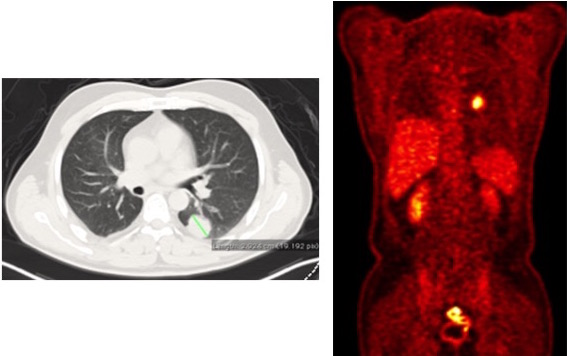

A 49-year-old male patient was operated on by the authors for a T4 (left atrium invasion) squamous cell carcinoma in the right lower lobe (Figure 1). pTNM was T4N0MO and four cycles of chemotherapy were given as adjuvant therapy. After four years of follow-up care, a chest CT showed a newly developed tumor (2.9cm) in the superior segment of the left lower lobe (Figure 2). Since there was no other increased FDG uptake in another part of the body, resection of the tumor was recommended by the Tumor Board.

The authors reserve segmental resections for lung cancer treatment in patients with limited pulmonary functions, resection of metastasis, or small-sized second primary lung cancer with no lymph node metastasis. Intraoperative frozen section pathology is performed at every step of the segmentectomy operation to avoid an incomplete oncological surgery. If appropriate in terms of the intraoperative findings and frozen section pathological analyses, the authors planned to perform a single-incision VATS (SIVATS) superior segmentectomy of the left lower lobe.